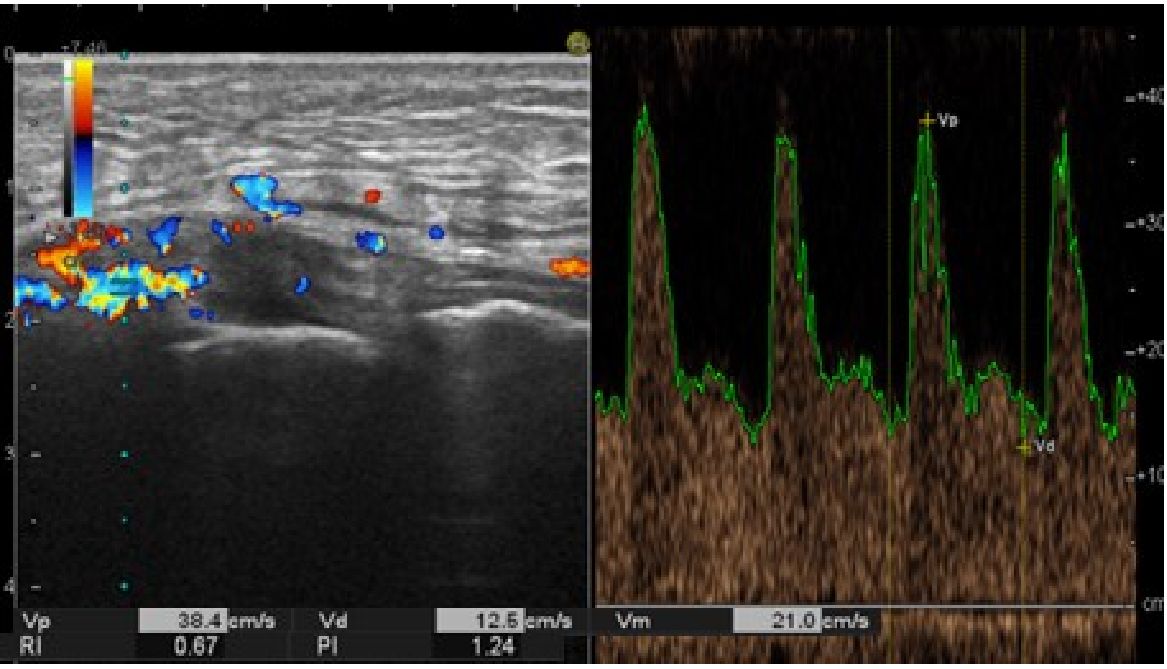

A clinical example may be sonograms of patient L., 29 years old. The diagnosis: injury of the anterior cruciate ligament of the right knee. Condition after reconstructive arthroscopy of ACL. In 3 days after arthroscopic reconstruction of ACL, USDS showed dilation of the popliteal vein on the right to 1.2 cm, it was patent along the available length and was easily compressible by the sensor. Velocity of venous outflow was reduced to 4.5 cm/sec. In the functional test with maximal manual compression of the popliteal vein, no increase in linear velocity of blood was found, and retrograde blood flow was recorded with duration up to 0.5 sec. Sural veins were dilated to 0.3 cm. In changing to vertical position the lumen of popliteal vein increased to 1.7 cm.

Figure 2 shows a sonogram of the medial part of knee joint in the frontal plane in 2 days after arthroscopic reconstruction of ACL. In longitudinal scanning, thickening and edema of synovium were determined in the projection of the lateral subligamentous space of the knee joint. Doppler scanning showed a local hypervascularization of the studied zone, the mean linear blood flow velocity (Vm) made 54.6% of the peak linear velocity (Vp), which was interpreted as evident vasodilatation of vessels.

Fig. 2. Sonogram of medial surface of the knee joint of patient L., 29 years old (triplex scanning mode is used)